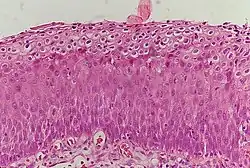

_normal_squamous_epithelium.jpg)

Historically, abnormal changes of cervical epithelial cells were described as mild, moderate, or severe epithelial dysplasia. In 1988 the National Cancer Institute developed "The Bethesda System for Reporting Cervical/Vaginal Cytologic Diagnoses".[12] This system provides a uniform way to describe abnormal epithelial cells and determine specimen quality, thus providing clear guidance for clinical management. These abnormalities were classified as squamous or glandular and then further classified by the stage of dysplasia: atypical cells, mild, moderate, severe, and carcinoma.[13]

CIN is classified in grades:[14]

| Histology Grade | Corresponding Cytology | Description | Image |

|---|---|---|---|

| CIN 1 (Grade I) | Low-grade squamous intraepithelial lesion (LSIL) |

|

| CIN 2/3 | High-grade squamous intraepithelial lesion (HSIL) |

| CIN 2 (Grade II) |

![]() | |

| CIN 3 (Grade III) |

![]() |